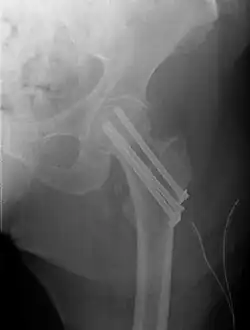

Fractures managed by closed reduction can possibly be treated by percutaneously inserted screws.[38]

Closed reduction may not be satisfactory and open reduction then becomes necessary.[43] The use of open reduction has been reported as 8-13% among pertrochanteric fractures, and 52% among intertrochanteric fractures.[44] Both intertrochanteric and pertrochanteric fractures may be treated by a dynamic hip screw and plate, or an intramedullary rod.[43]